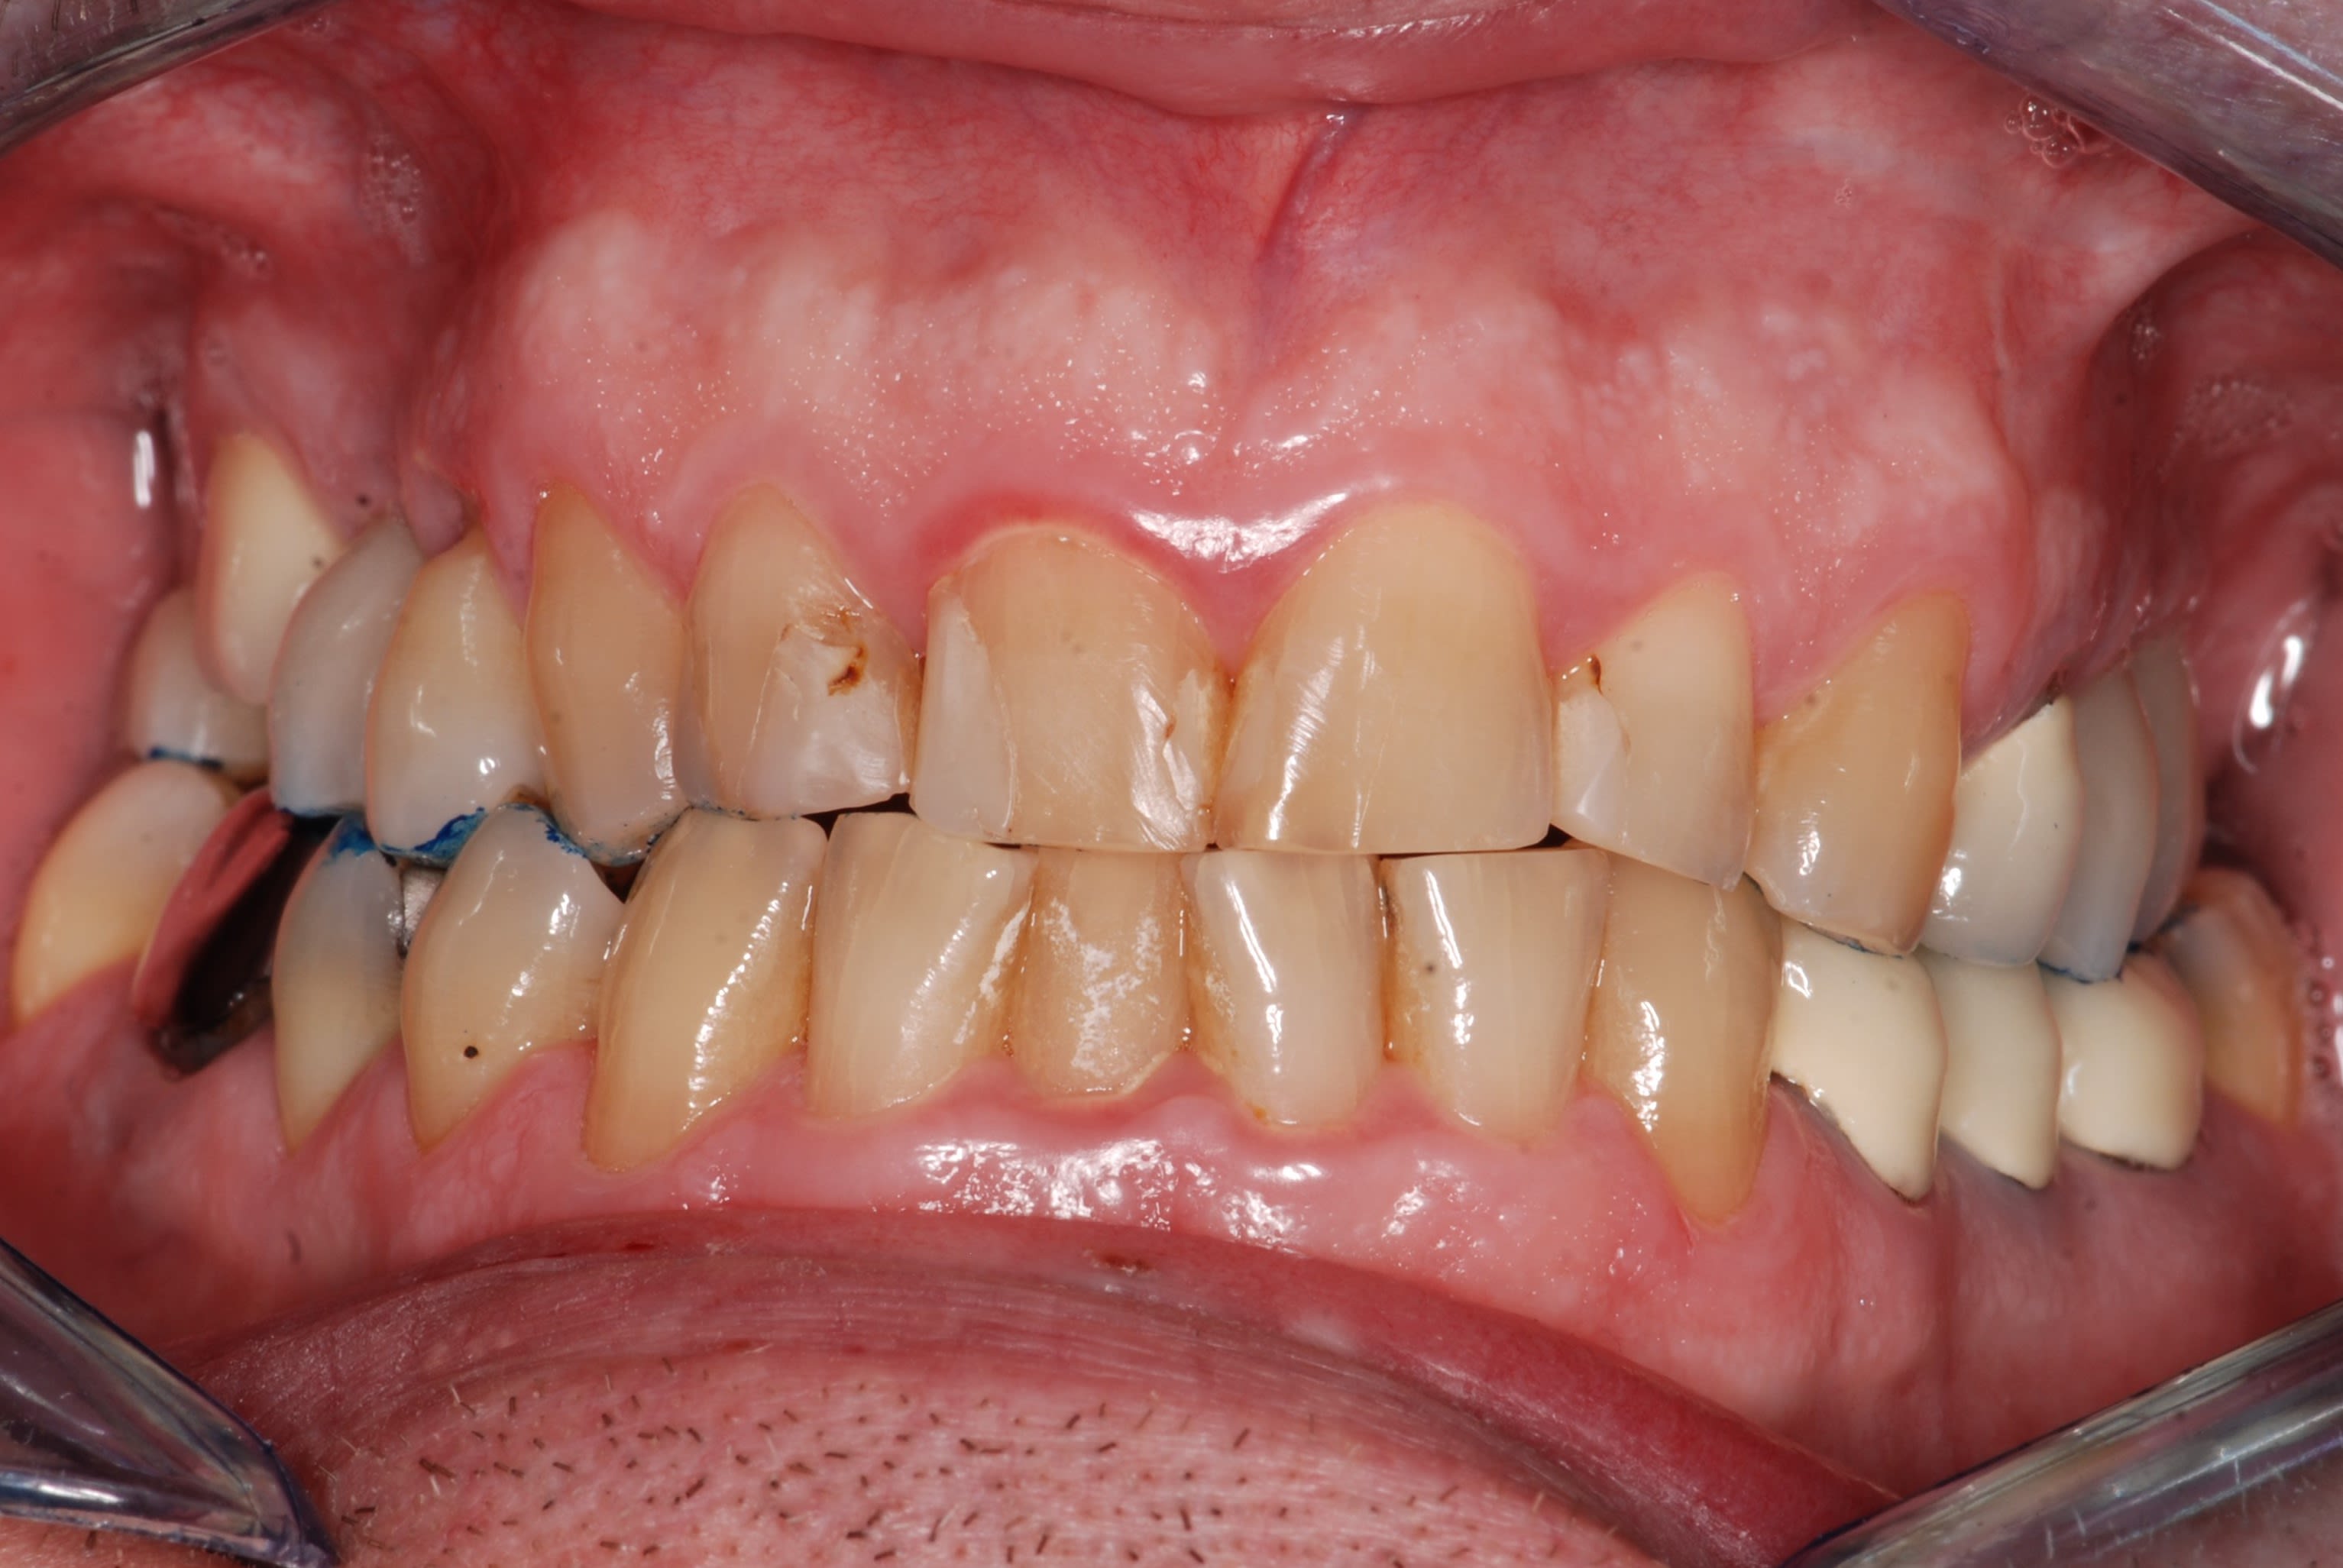

Ce patient vient me voir pour une dent "qui est remontée dans sa gencive" associé à des douleurs à la mastication

Effectivement en bouche la 16 est complètement ingressée.

de toute évidence les couronnes sur implants ont étés mises après la couronne de 6 .

ou alors la 6 n est pas alignée sur l arcade .

meme si elle avait ingressé , admettons , les implants eux , n ont pas bougé , or il n y a pas l espace pour la 6 .

Comme promis, voici les photos du cas.

Comme je disais on dirait que la dent est remontée avec tout son parodonte...